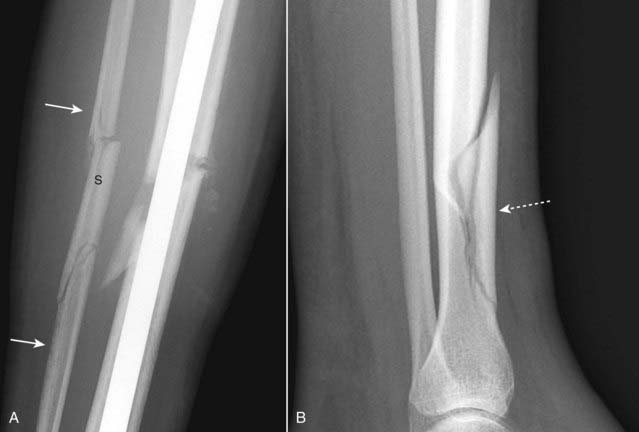

A segmental fracture is a comminuted fracture in which a portion of the shaft exists as an isolated fragment (Fig. 22-6A).

Figure 22-6 Segmental fracture and butterfly fractures.

These are two comminuted fractures. A, This is a segmental fracture in which a portion of the shaft exists as an isolated fragment. Notice how the fibula has a center segment (S) and two additional fragments, one on either side (solid white arrows). B, A butterfly fragment is a comminuted fracture in which the central fragment has a triangular shape (dotted white arrow).